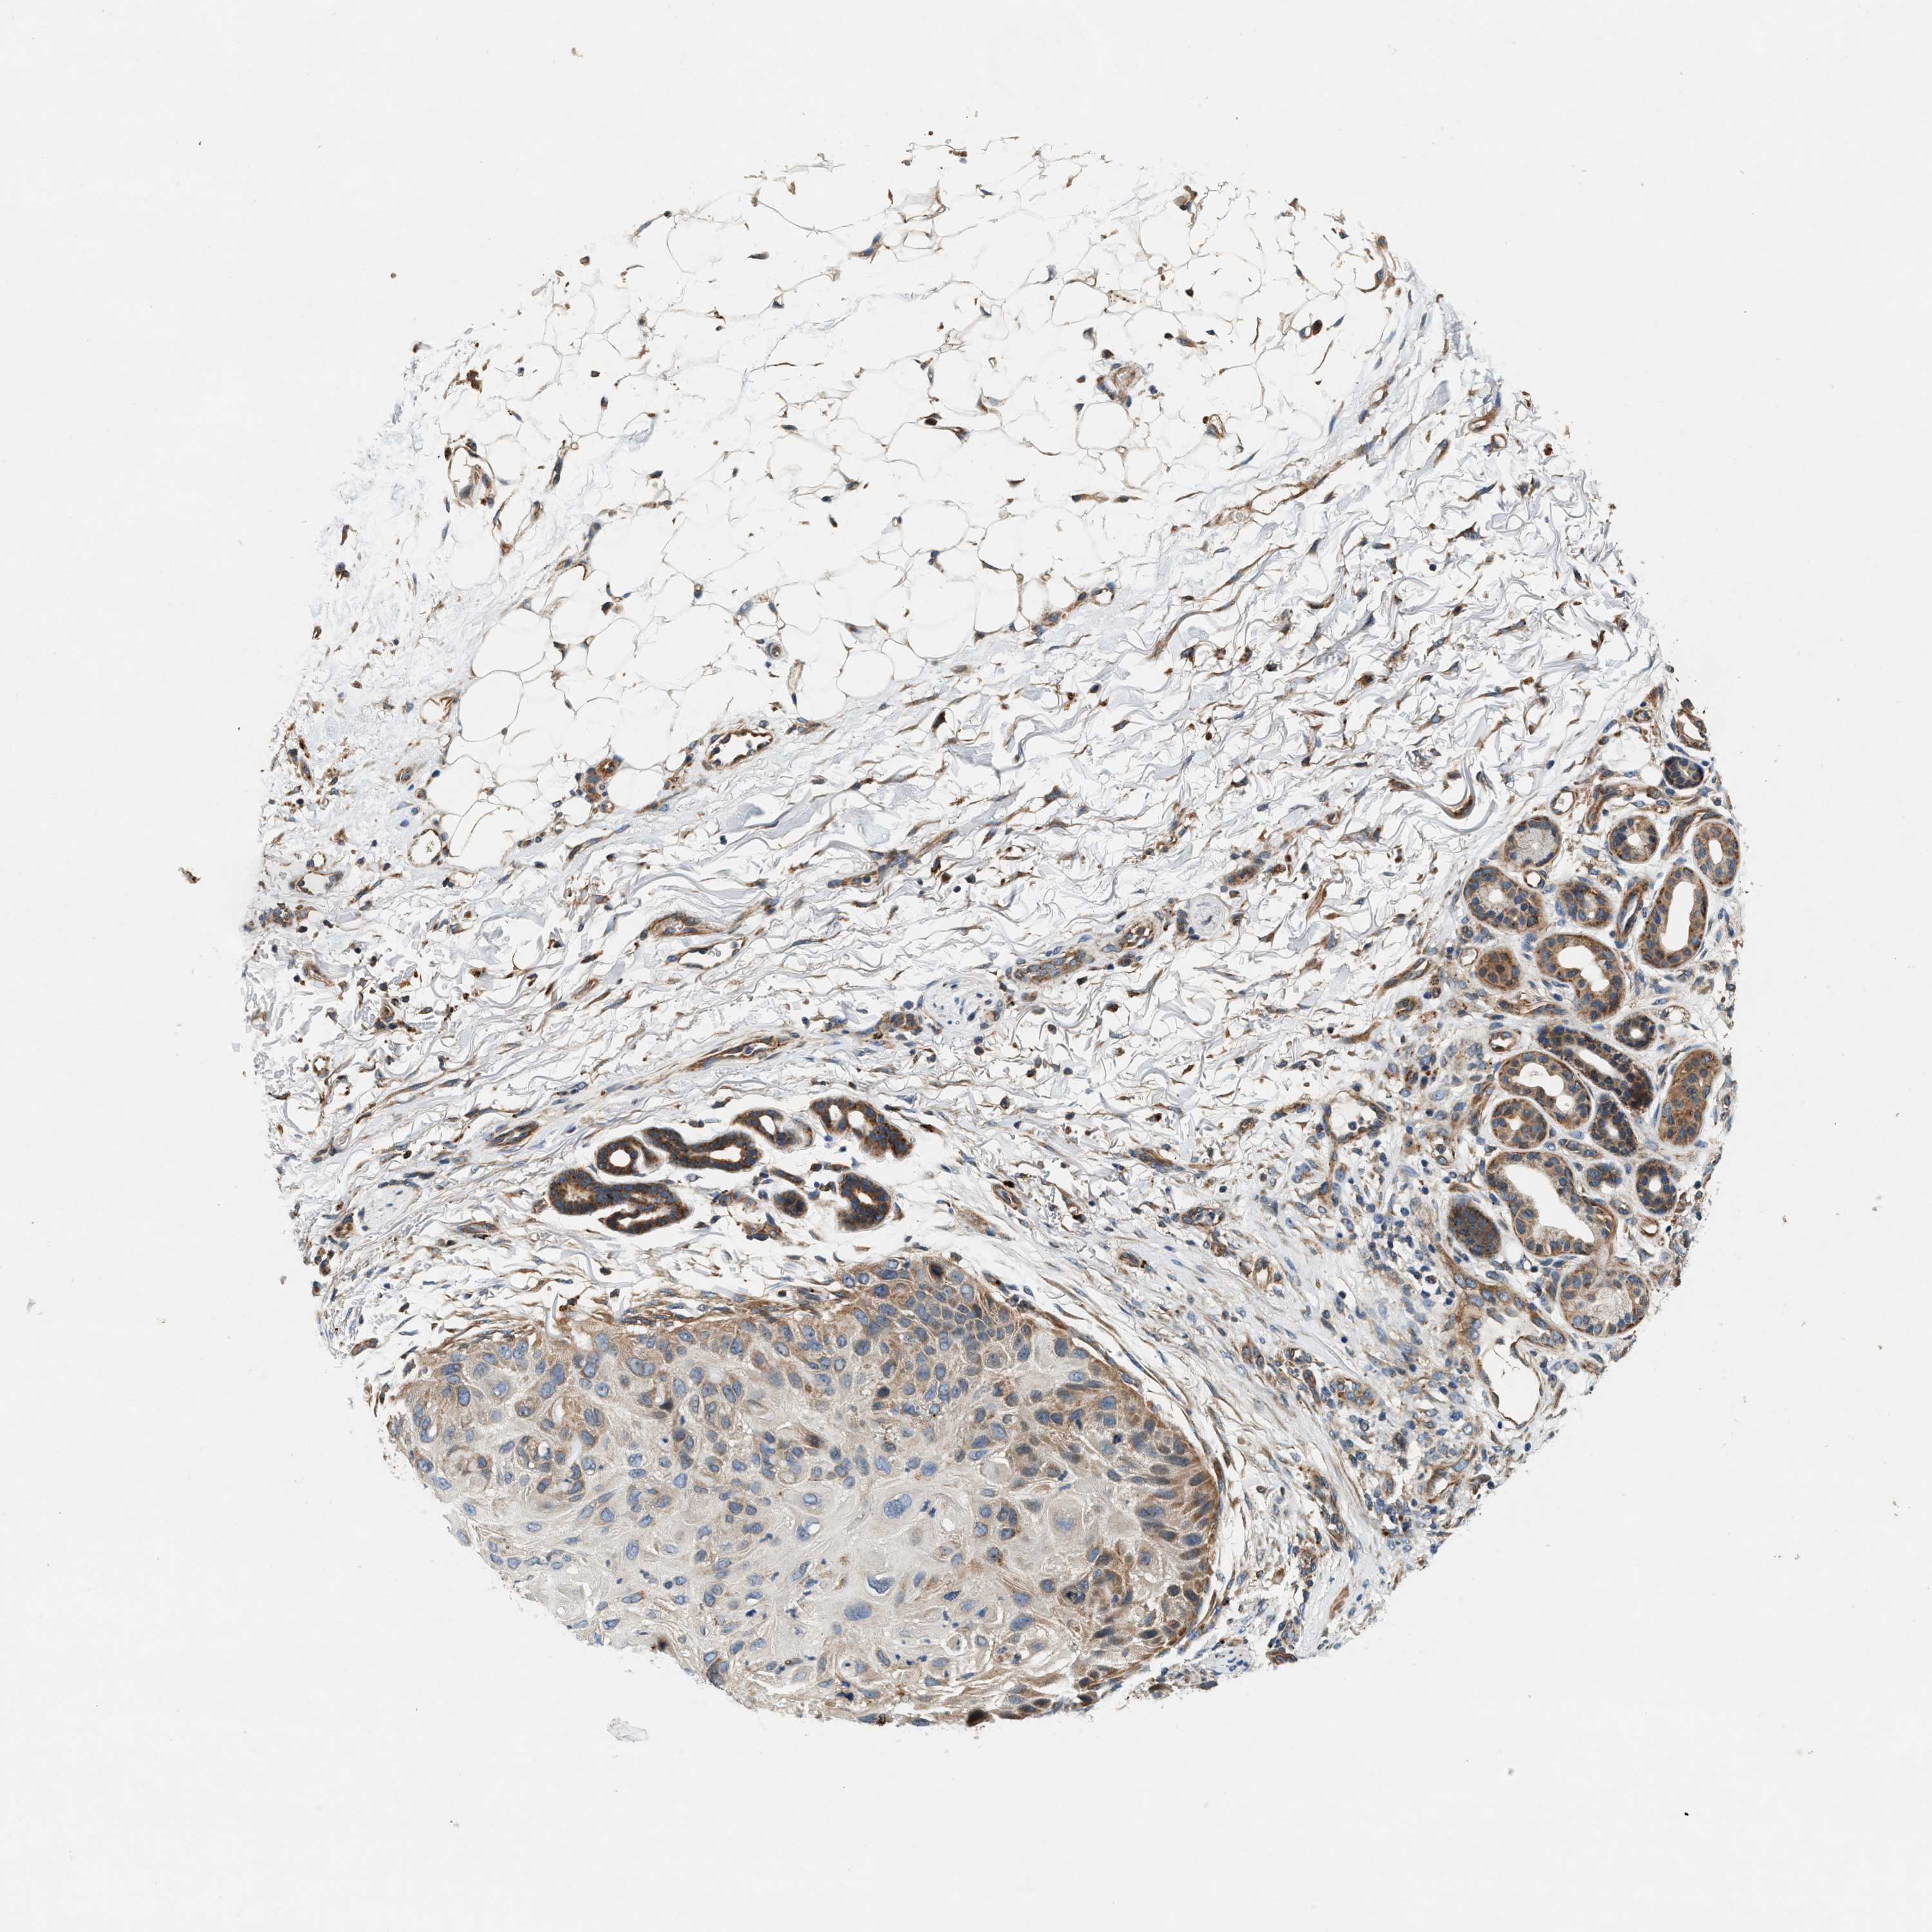

Basal cell and squamous cell cancer

SKIN CANCER - Protein expressioni

A mouse-over function shows sample information and annotation data. Click on an image to view it in a full screen mode. Samples can be filtered based on level of antibody staining by selecting one or several of the following categories: high, medium, low and not detected. The assay and annotation is described here.

Antibody stainingi

Antibody staining in the annotated cell types in the current human tissue is reported as not detected, low, medium, or high, based on conventional immunohistochemistry profiling in selected tissues. This score is based on the combination of the staining intensity and fraction of stained cells.

Each image is clickable and will lead to virtual microscopy that enables deeper exploration of all samples and also displays staining intensity scores, fraction scores and subcellular localization as well as patient and tissue information for each sample.

Antibody HPA016758

Staining

High

Medium

Low

Not detected

Intensity

Strong

Moderate

Weak

Negative

Quantity

>75%

75%-25%

<25%

None

Location

Nuclear

Cytoplasmic/membranous

Cytoplasmic/membranous,nuclear

Basal cell carcinoma